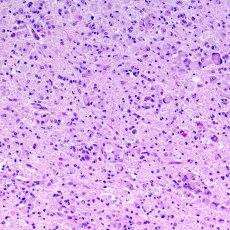

Las leucodistrofias son un grupo de trastornos genéticos raros que afectan el sistema nervioso central, el que está formado por su cerebro y médula espinal. Las leucodistrofias dañan la sustancia blanca (o materia blanca) de su sistema nervioso central. La sustancia blanca incluye:

- Fibras nerviosas: Conectan las células nerviosas, también se conocen como axones

- Mielina: Capa de proteínas y materia grasa que recubre y protege las fibras nerviosas. También ayuda a acelerar las señales entre las células nerviosas

Cuando la sustancia blanca está dañada, puede hacer más lentas o bloquear las señales entre las células nerviosas. Esto puede causar muchos síntomas diferentes, incluyendo problemas de movimiento, vista, audición y pensamiento.